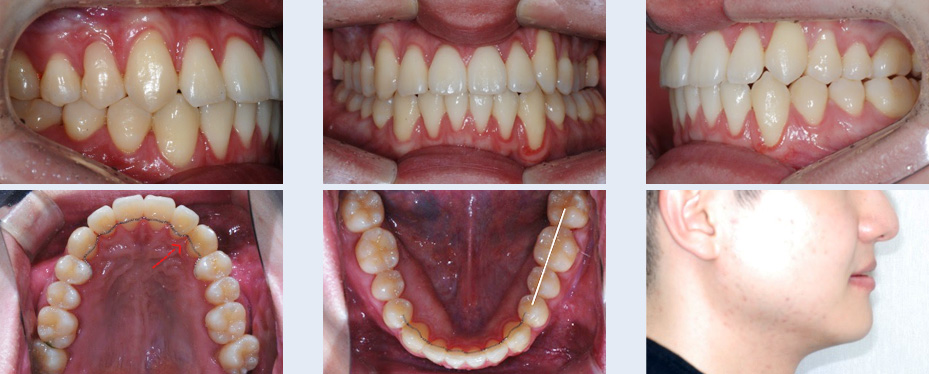

고르지 않은 앞니의 교정 치료를 위해 내원한 26세 여성입니다. 상대적으로 위턱의 공간이 아래턱에 비해 좁아

비대칭이 나타난 상황이었으나, 이를 빼거나 양악수술을 원치 않으셔서 그 대안으로 위턱뼈의 공간 확장

(MARPE)과 미니스크류를 이용하여 아래 치아를 후방 이동시킨 후 공간을 확보하는 치료 계획으로

진행되었습니다.

발치와 양악수술 없이 자연스럽고 고른 치열을 갖게 되어 앞니의 심미적인 개선을 기대한 환자 분의 만족감이

높았습니다.